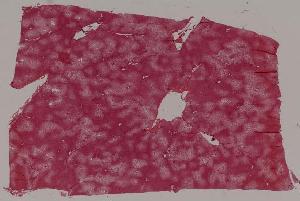

18.假膜性肠炎